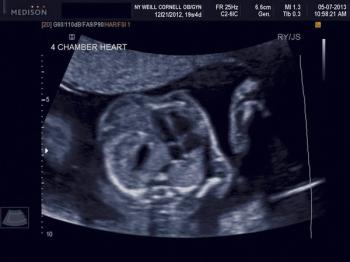

While several fetal anomalies can be diagnosed early in the pregnancy, second-trimester ultrasound can identify or exclude even more conditions. The second slideshow of our ultrasounds collection includes the second-trimester anomalies of the body and limbs that shouldn't be missed.